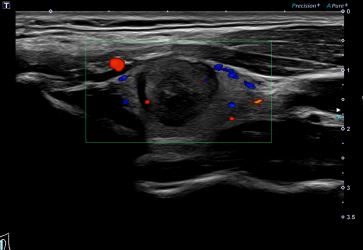

상기환자 갑상선 외부검사이상으로 내원하신 30대 여성분으로

의심스러운 갑상선 좌엽 세침검사 결과 갑상선암으로 진단되었습니다.